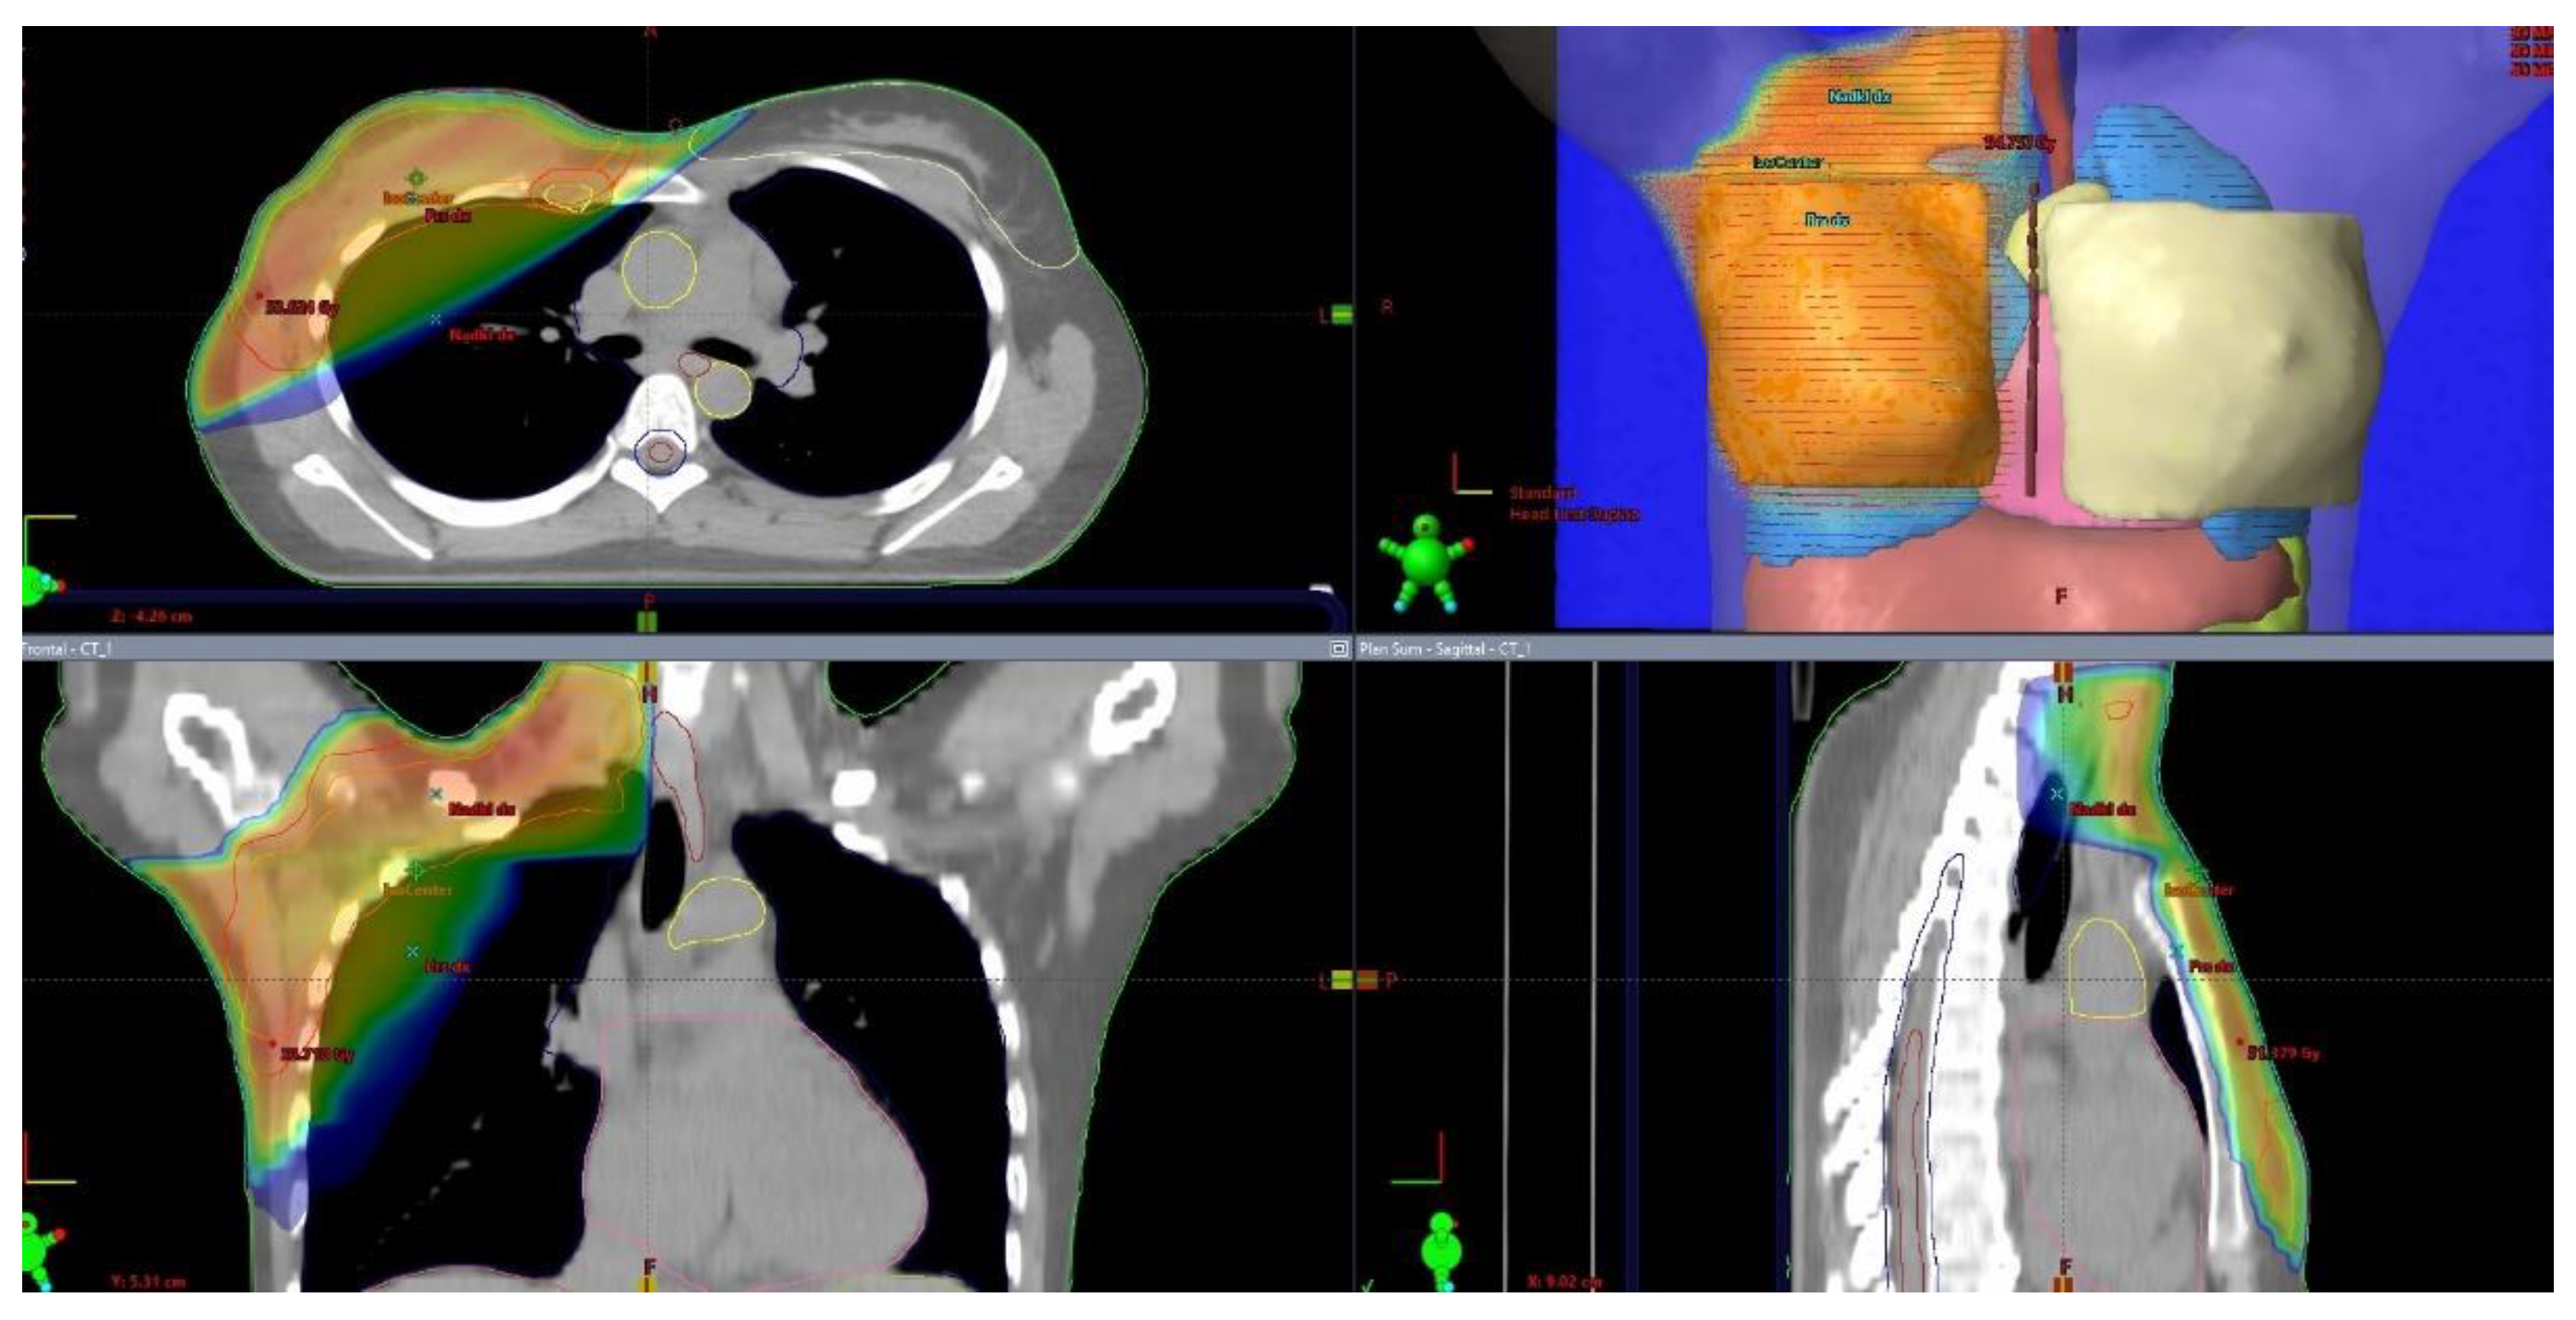

Figure 5. Postmastectomy radiotherapy (PMRT) with axillary, internal mammary, and medial supraclavicular lymph node irradiation. .

The progress in radiotherapy is based mostly on the use of new technologies. Currently. external beam radiation is performed using linear accelerators after computed tomography-based imaging (Figure 1) and 3-dimensional planning using sophisticated technologies, including intensity-modulated radiation therapy (IMRT). The control of the accuracy of the dose delivery can be increased with image-guided radiation therapy (IGRT, Figure 2). The dose to the heart can be substantially decreased by delivering radiation in deep inspiration (Figure 3) or prone position [4,5].

Internal mammary node irradiation (Figure 5) is another controversial topic. Individual trials did not demonstrate an overall survival advantage of this therapy, and benefits and risks should be carefully weighted. The EORTC 22922/10925 phase 3 trial enrolled 4004 patients younger than 75 years with unilateral, histologically verified stage I to III breast cancer and axillary lymph node involvement or medial tumor location treated with mastectomy or breast-conserving surgery and axillary staging. The patients were randomized at a 1:1 ratio between internal mammary and medial supraclavicular lymph node irradiation with the dose of 50 Gy in 25 fractions or no such treatment. The administration of internal mammary and medial supraclavicular lymph node irradiation resulted in lowering the risk of breast cancer death or any recurrence at 15 years, but no overall survival benefit was observed [30].